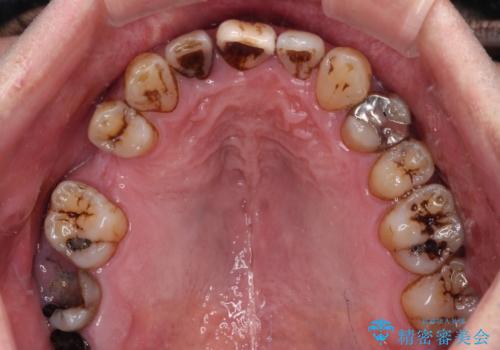

- むし歯治療途中で放置された歯が多く、スペースができたり歯が寄って来たりしているのを気にして来院された患者様です。

矯正治療を行いながら、欠損部はインプラントによる補綴治療を希望されたため、補助装置を用いたワイヤー矯正によりスペースを確保しながら歯列を整え、適宜インプラントを埋入していくこととしました。